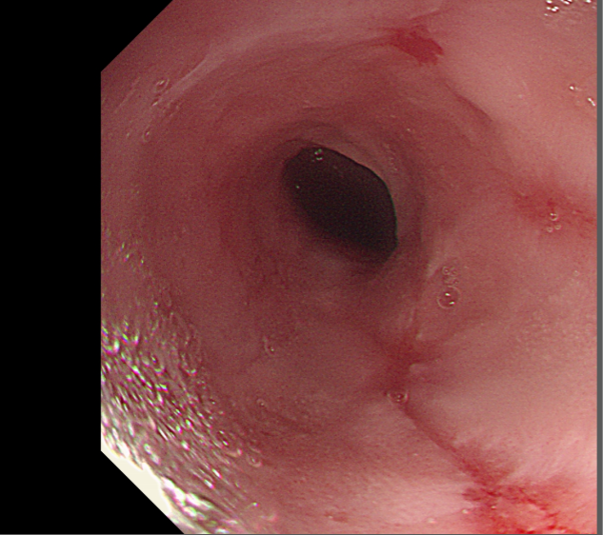

Figure 1: Reflux oesophagitis.

- Los Angeles (LA) Classification for Erosive Esophagitis:

|

Grade |

Endoscopic Findings |

A |

Mucosal break ≤ 5 mm that does not extend between folds |

B |

Mucosal break > 5 mm but does not extend between folds |

C |

Mucosal break continuous between folds, < 75% of circumference |

D |

Mucosal break involving ≥ 75% of the esophageal circumference |